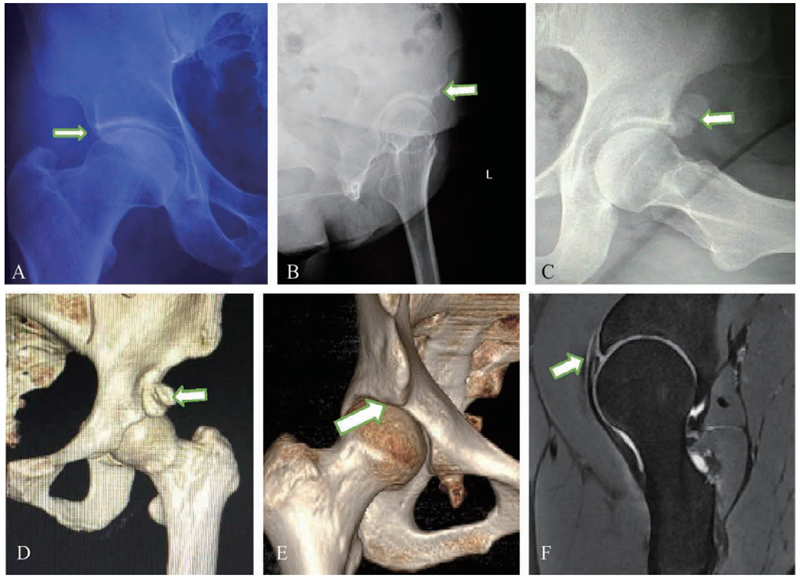

2 AIIS形态的影像学表现

A.骨盆前后位X线片显示AIIS和髋臼前缘形成部分重叠,可能被忽视或被判读为交叉征阳性;B.65°假斜位X线片,可以显示AIIS的大致形态;C.DunnX线片显示AIIS异常骨突和头颈部的撞击关系;D.CT三维重建显示AIIS的形态;E.CT三维重建显示AIIS和头颈部Cam畸形同时存在,使得屈髋位棘下间隙更加狭窄,盂唇受到对冲挤压;F. MRI显示盂唇撕裂